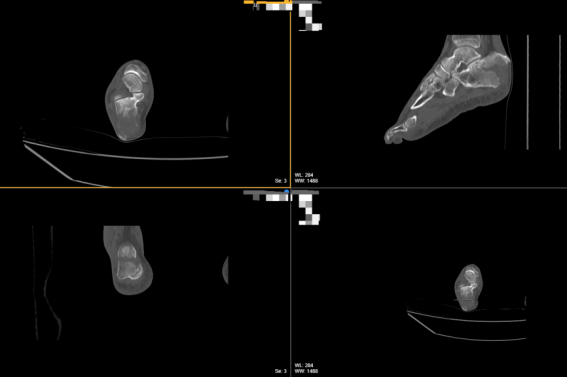

右足部CT平扫MPR

术中使用到钢丝引导器,从内侧切口处进入紧贴跟骨下骨面从外侧最下侧切口穿出,用一根单股超高分子量聚乙烯缝线穿入钢丝引导器将其引出,依次从各切口穿出,近端从跟腱下跟骨表面穿出,环绕跟骨一圈止于内侧切口,用单股超高分子量聚乙烯缝线带出一根双股超高分子量聚乙烯缝线环绕跟骨,各切口处留出约3-4cm长度缝线(方便于后期收紧缝线),用尖端复位钳通过后方小切口,一钳臂置于结节背侧,另一尖端穿过足跟脂垫,缓慢合拢钳臂,使骨折复位,透视下确认骨折复位可。

NICE结收紧缝线,用血管钳插入线圈,通过一挑一拉,逐渐拉紧收紧缝线,通过NICE结的滑动锁定机制实现动态加压,将导针自跟骨结节后下方钻入,透视确认导针位置满意后,沿导针拧入1枚φ4.5x50的空心金属接骨螺钉。最后将线头埋于皮下。再次透视确认骨折复位良好、内固定位置满意后,缝合切口,无菌敷料包扎。